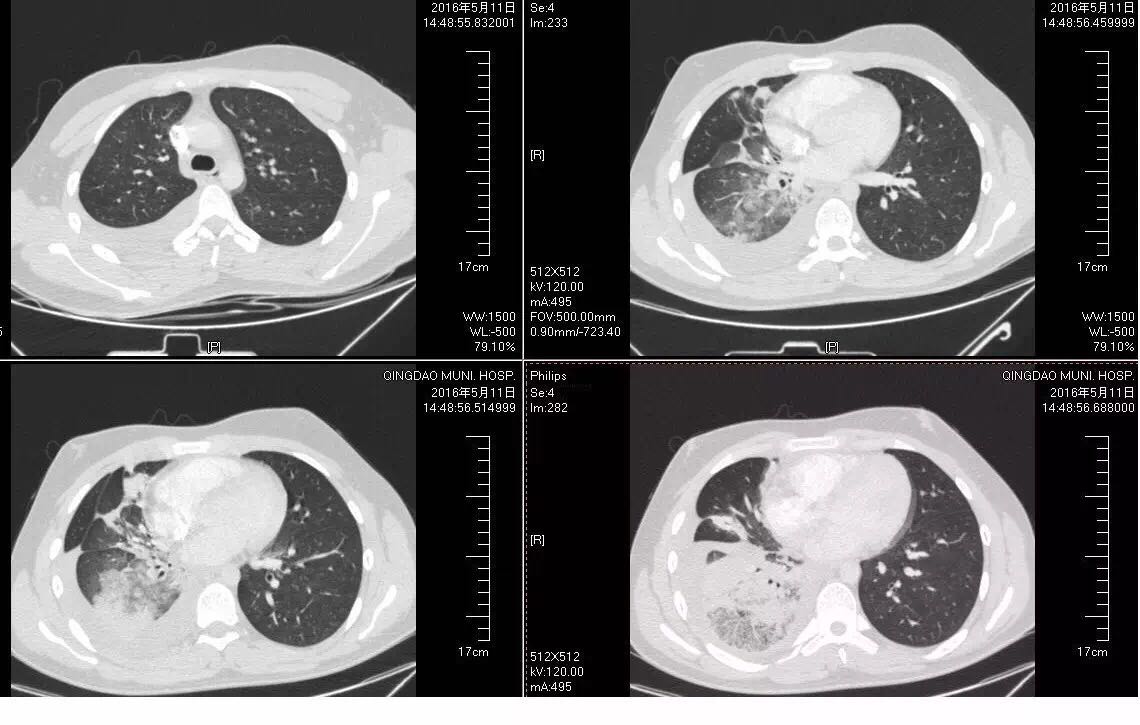

图1 入院查体T: 37.8 ℃,听诊右肺呼吸音低,未闻及干湿性啰音,心率68次/分。 诊断: 社区获得性肺炎,非重症 ; 2.胸膜炎; 3.胸腔积液。 病人青年男性,考虑抗感染力度不够、覆盖不足或结核可能,另外也考虑到我国支原体对阿奇霉素耐药率高的问题,给予磷霉素联合米诺环素抗感染,辅以止咳、化痰等治疗。病人于入院次日晨咳鲜红色血痰10ml,体温升至38.9℃,加用奥司他韦抗病毒,并予云南白药止血对症治疗。同时完善相关检查,降钙素原0.1ng/ml;血常规:WBC 10.78×109/L,C反应蛋白109.60mg/L;D-二聚体定量3.45ug/ml,我院正常值为0---0.5 ug/ml 白蛋白43.28g/L;血沉61.00mm/H; ANA谱及ANCA均未见异常;肺炎支原体抗体阴性;肺炎链球菌抗原定性阴性;24h痰液未找到抗酸杆菌。 此后病人发热、咯血无缓解,PPD试验阴性,行胸腔超声检查,报胸腔积液,液深1.8cm,建议胸腔穿刺、支气管镜检查进一步明确,病人家长均拒绝。考虑病人年少,无持续卧床史,双下肢无水肿,心电图无异常改变,D-二聚体升高考虑感染所致,加用头孢他啶进一步覆盖G-杆菌。病人体温峰值出现下降,咯血、胸痛仍无好转,入院第5天复查血常规:WBC 7.00×109/L,C反应蛋白149.16mg/L;D-二聚体定量3.95ug/ml;肌钙蛋白、BNP正常;血气分析示pH为7.52,PaO2为136mmHg,PaCO2为30.9mmHg(吸氧流量为2L/分);痰培养、血培养均为阴性。 再次评估病情,经较强抗感染治疗患者仍有发热、胸痛、咯血,D-二聚体较前升高,追问病史近期有夜间长时间端坐玩电脑诱因,考虑肺栓塞不能排除,停用云南白药。病人家长初拒绝CTPA检查,完善下肢血管超声未见异常,遂先行超声引导下胸腔穿刺,抽出不凝血,胸水常规:白细胞 1878×106/L,N80%,蛋白定性实验4+;胸水腺苷脱氨酶18.02U/L。再次与病人家长沟通后于入院第6天行CTPA检查,提示右下肺动脉栓塞,右肺片状影及胸腔积液均较前加重(见图2、3)。

图2

图3